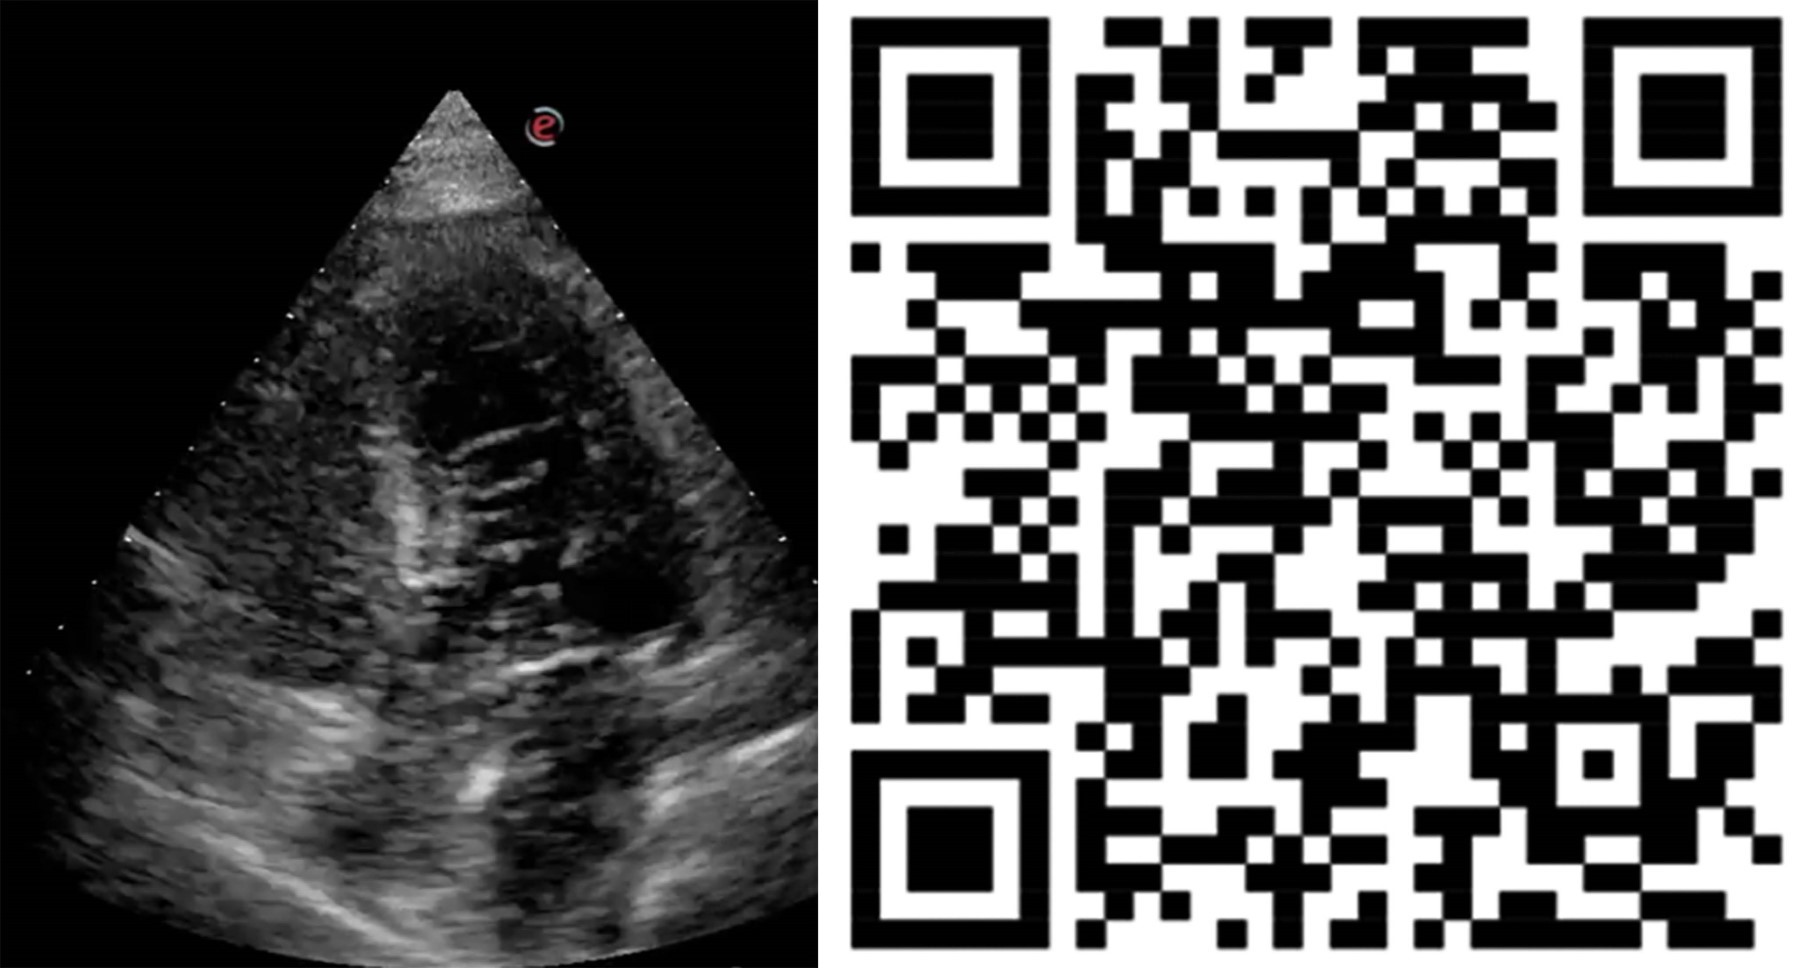

Figure 3